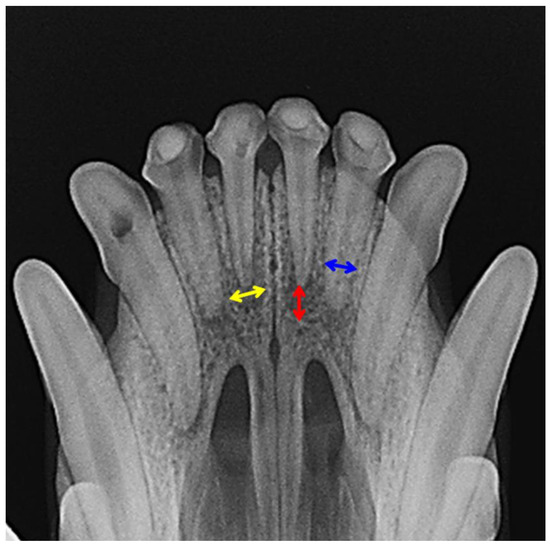

2.2.2. X-ray Analysis and Histology

3.2. Evaluation of Animal Experiment